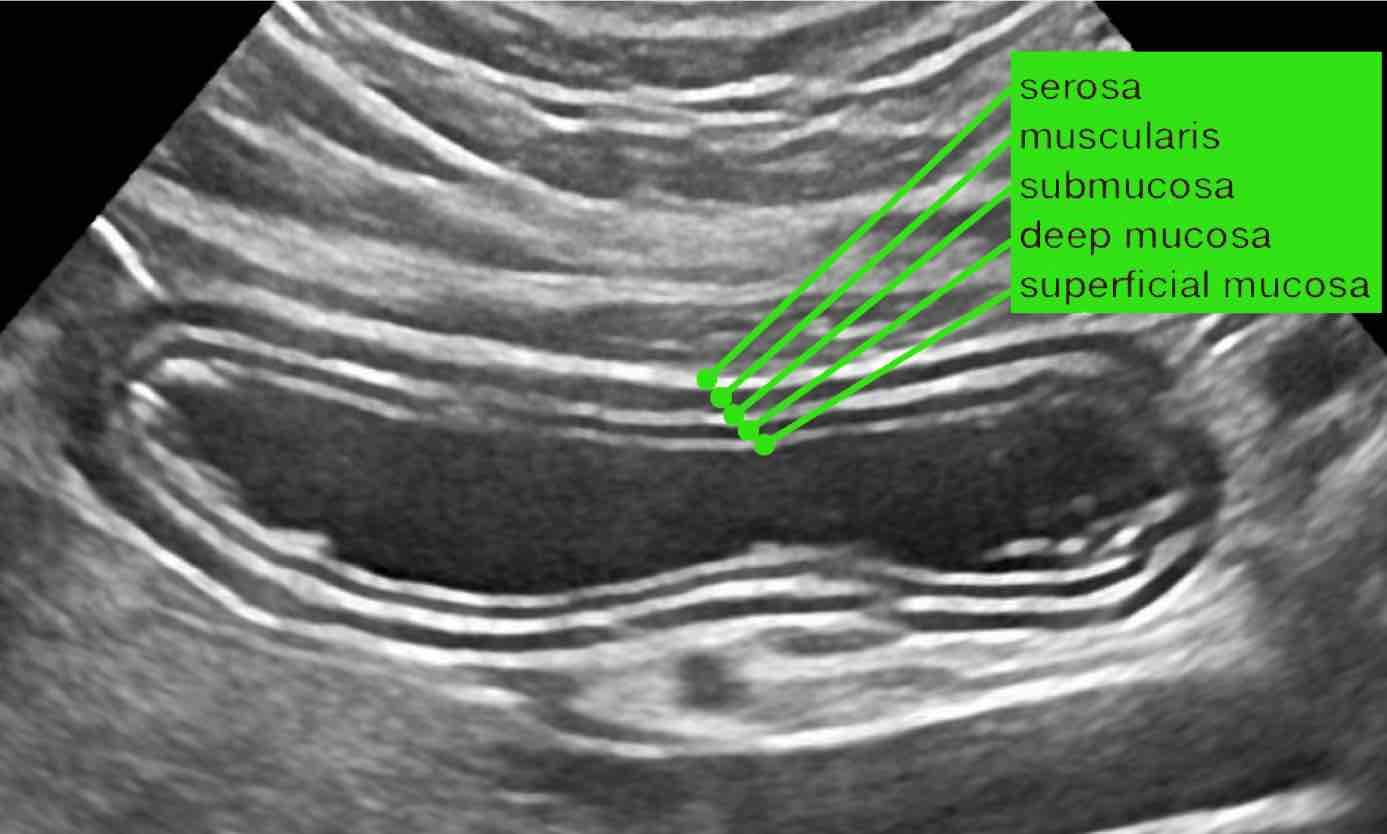

Cấu trúc siêu âm của thành ruột bình thường có hình thái đặc trưng gồm năm lớp với độ hồi âm xen kẽ nhau, tương ứng chặt chẽ với các lớp mô học của thành ruột.

Cấu trúc siêu âm này về cơ bản là đồng nhất từ dạ dày đến trực tràng.